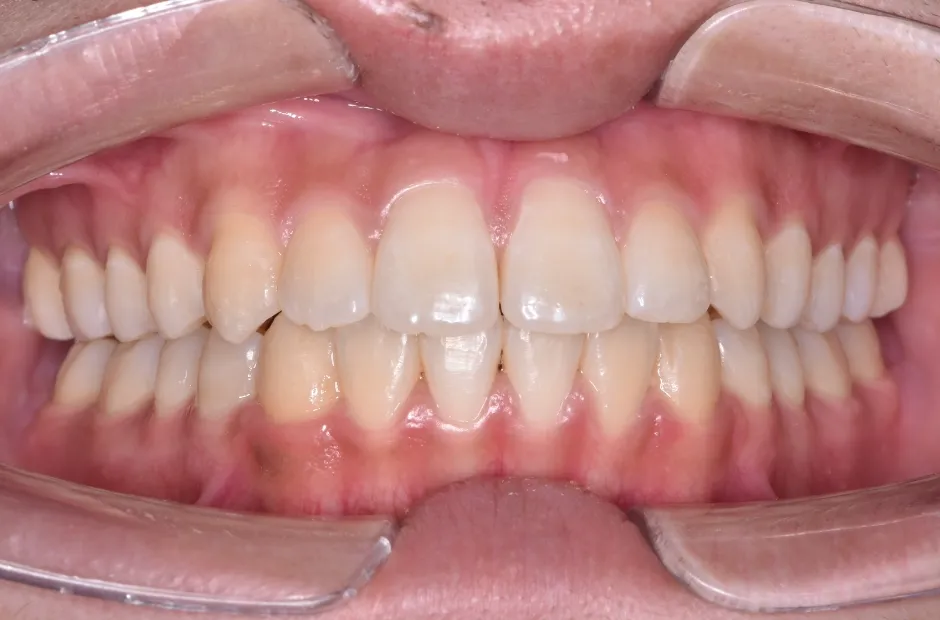

治療後